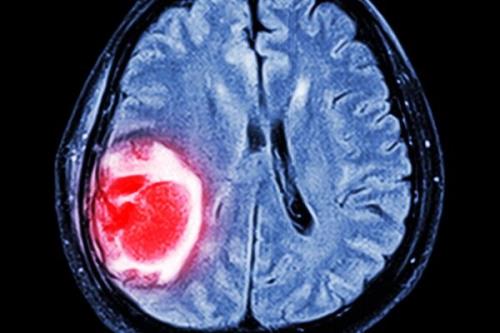

نانوذرات گیاهی با سرطان مرگبار مغز مقابله می کند